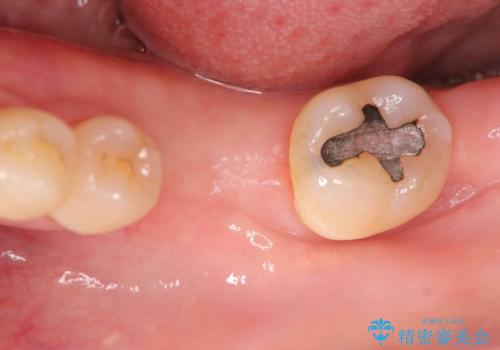

根尖性歯周炎|分岐部病変|パーフォレーション|インプラントで治療

- レントゲン検査にて、根尖および側枝付近に骨の透過像が認められました。

さらに精査したところ、根のパーフォレーション(根に穴が開いてしまっている状態)が確認されたため、

患者様と相談のうえ、インプラントによる治療をご希望され治療を行いました。